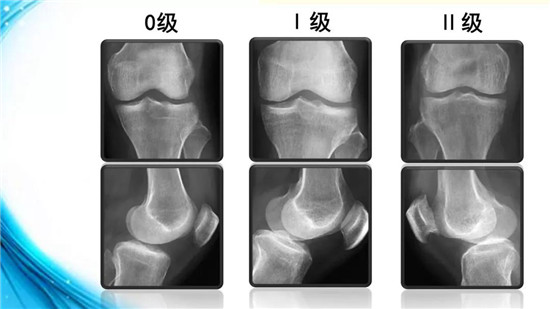

下面,我们来了解一下膝骨性关节炎的分级、分型与分期。根据X线所示,可对膝骨性关节炎进行分级。

0级为正常膝关节。Ⅰ级关节间隙可疑狭窄,可能有骨赘。Ⅱ级关节间隙轻度变窄,有明显骨赘。